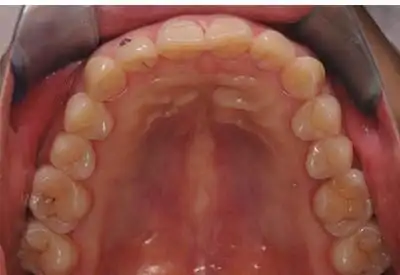

口腔美学临床影像规范介绍和解读